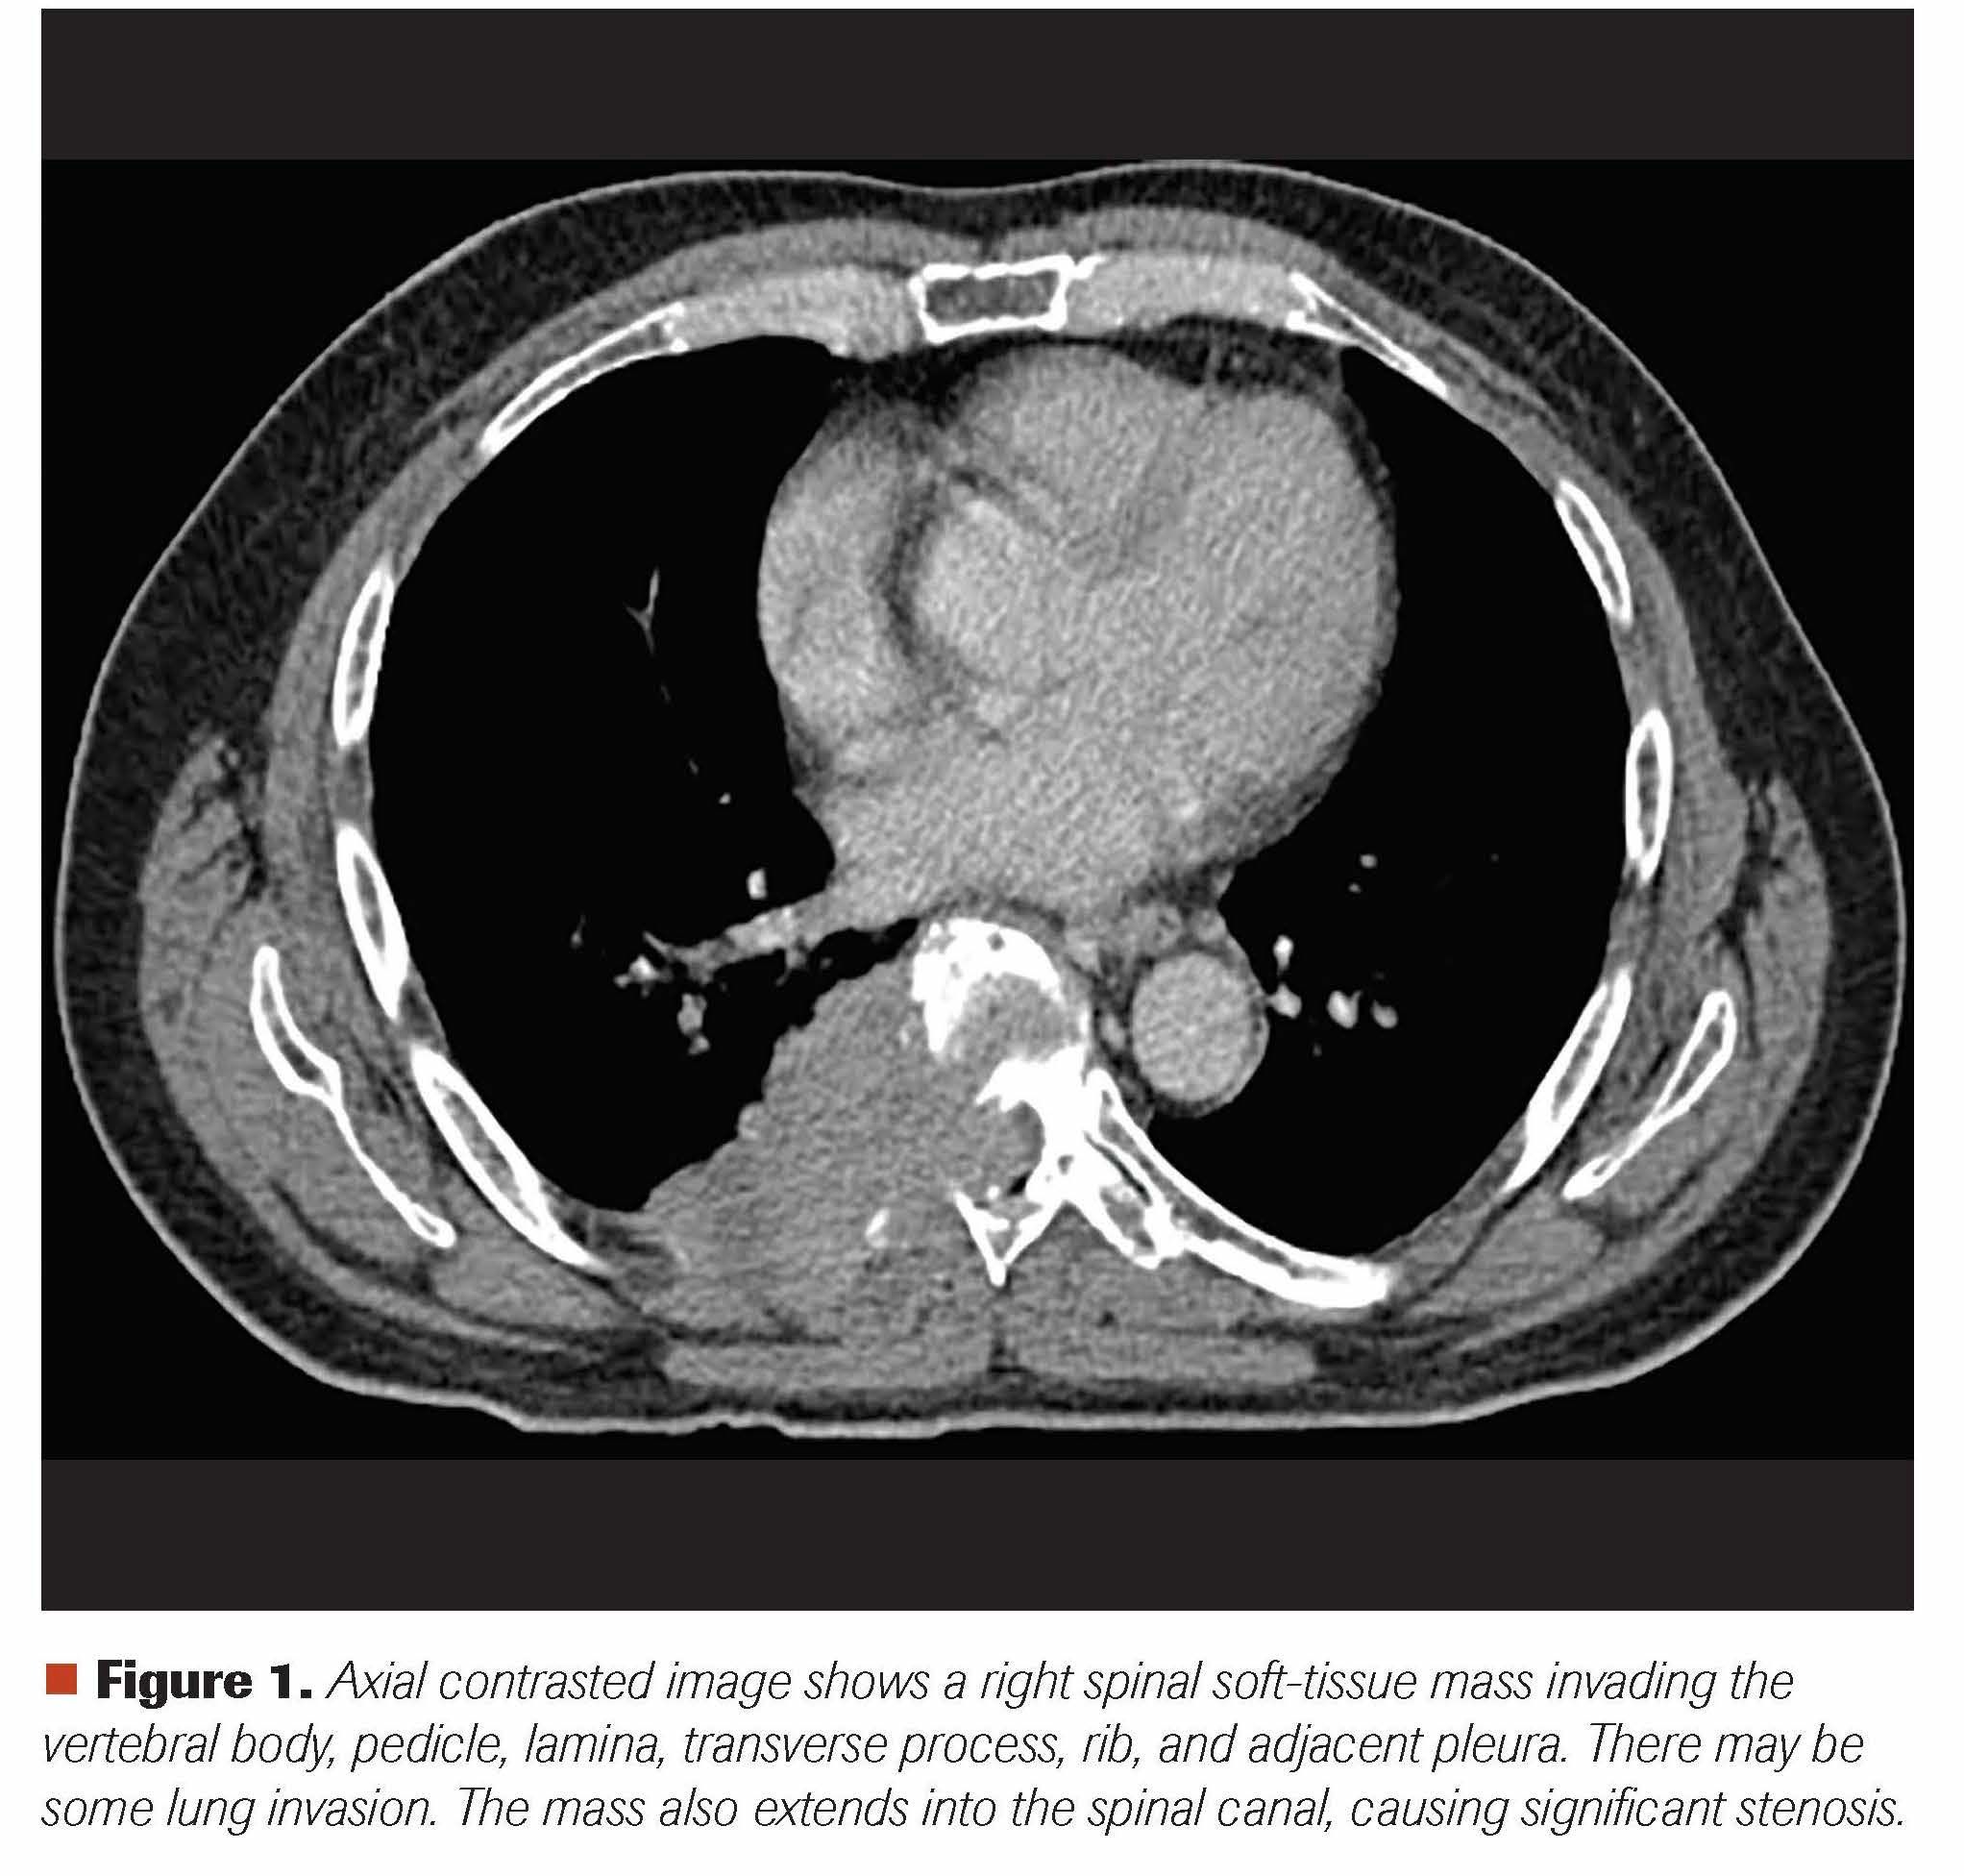

A man aged 65 years presented with right-sided lower thoracic back pain of 1-month duration; it was brought upon by pushing a sliding door in his garage. While it was initially a sharp pain, it transformed into a dull continuous ache radiating to his right rib and right hemithorax. He thought he pulled a muscle and saw a chiropractor, but he received no relief despite 5 chiropractic treatment sessions. During all this time he did not notice any extremity weakness or bladder or bowel incontinence, but he eighth area. He next saw his primary care provider, and a CT scan of his chest revealed a soft tissue mass measuring 6.2 x 3.5 x 2.8 cm in the posterior mediastinum/posterior chest wall with involvement of the posterior eighth rib and adjacent T8 vertebral body, with extension into the right aspect of the spinal canal (Figure 1). Further evaluation with an MRI of the thoracic spine confirmed the T8 compression and associated soft-tissue mass causing moderate-to-severe central spinal stenosis (Figure 2). A CT-guided biopsy of this large destructive mass revealed sheets of plasma cells (Figures 3 and 4). Further work-up revealed abnormal serum protein electrophoresis with a 3.53 g/dL monoclonal serum paraprotein, abnormal serum immunoglobulins (Ig; 5365 mg/dl; IgA, 23 mg/dL; IgM, 11 mg/dL), abnormal free light chains (λ free light chain, 14.6 mg/L; λ free light chain, 146.2 mg/L; ratio, 0.1), and abnormal λ-2 microglobulin of 4.9 mg/L. Bone marrow aspiration and biopsy revealed plasma cell myeloma comprising 40% of marrow cellularity (Figures 5 and 6). Staging work-up was completed with a PET-CT, confirming large osseous destructive mass at T8 level (Figure 7).

Figure 1. Axial contrasted image shows a right spinal soft-tissue mass invading the vertebral body, pedicle, lamina, transverse process, rib, and adjacent pleura. There may be some lung invasion. The mass also extends into the spinal canal, causing significant stenosis.